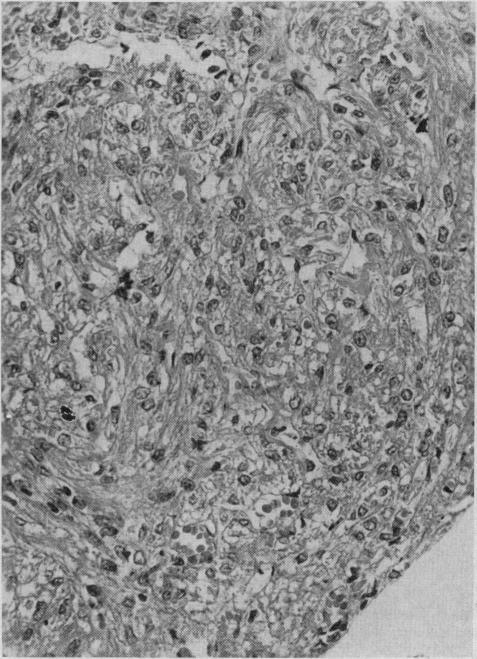

Pulmonary and lymph node myomatosis: review of the literature and report of a case.

Can Med Assoc J. 1967 Feb 18;96(7):420-4.